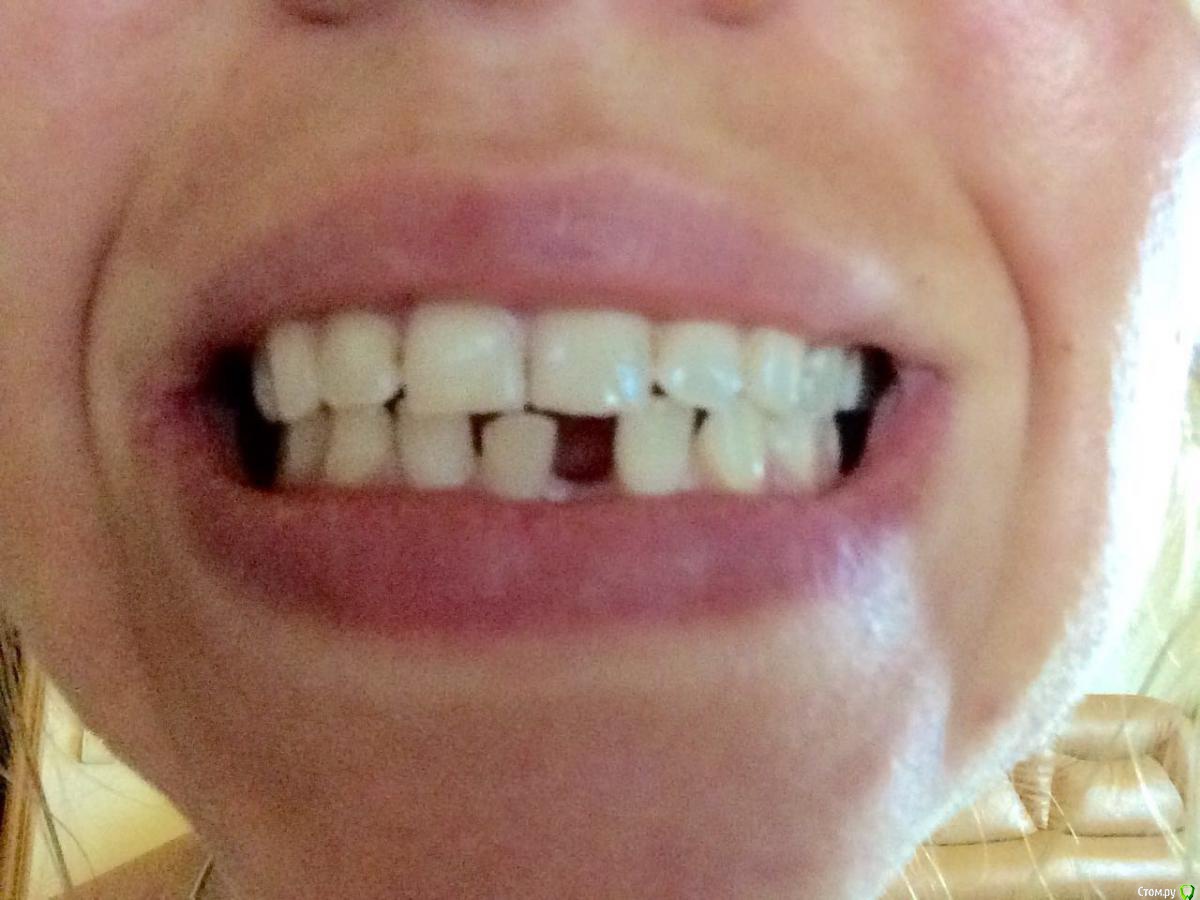

svetanik8 Опубликовано 25 мая, 2017 Поделиться Опубликовано 25 мая, 2017 Уважаемые врачи, прошу совета, чтобы определиться с тем, что делать.Году на 28м узнала, что у меня неправильный прикус (прямой), с детства отсутствует нижний передний зуб (детская травма, на тот момент врачи сказали, что зубы сойдутся, все будет ок, не сошлись, но мало кто видит, что его нет, улыбка как бы не такая низкая, чтобы открывать нижний ряд зубов).Лет в 25 удалили первую 6ку в нижнем ряду, спустя пару лет вторую симметрично, итого имею три проблемы, которые нужно решить (имплантация либо мост). Посетила пару врачей, один ортодонт предложил установить брекеты только на несколько нижних зубов с тем, чтобы сделать место для импланта на месте отсутствующего переднего, так как прикус меня 30 лет до этого не беспокоил, мне зубы кажутся ровными. Врач имплантолог в этой же клинике предложил по всем трем отсутствующим зубам сделать какое-то расщепление с подсадкой, при котором сразу же ставится имплант, причем обе шестерки предложил объединить в одну операцию, чтобы сэкономить на какой-то мембране.Второй врач сказал делать подсадку ткани по всем трем, по брекетам ничего не прокомментировал, отдельно нужно общаться с ортодонтом.И еще один врач тоже сказал, что нужно делать подсадку костной ткани, что расщепление ему не очень нравится в принципе, что может отломаться кость и тп. Подсадка костной ткани очень недешевая процедура (или я ходила в такие клиники дорогие, не знаю). Вопрос, стоит ли в моем случае делать импланты (по каждому зубу) или где-то лучше мост (например, семерка слева под коронку уже, там ползуба нет).Прилагаю снимки ОПТГ и КТ (скриншоты, если нужны другие ракурсы скажите, пока не разобралась как их делать).Отдельный вопрос по брекетам, не знаю выносить ли в отдельнуютему, проблема комплексная. На всякий случай еще фото обычные зубов.Спасибо заранее. Ссылка на комментарий